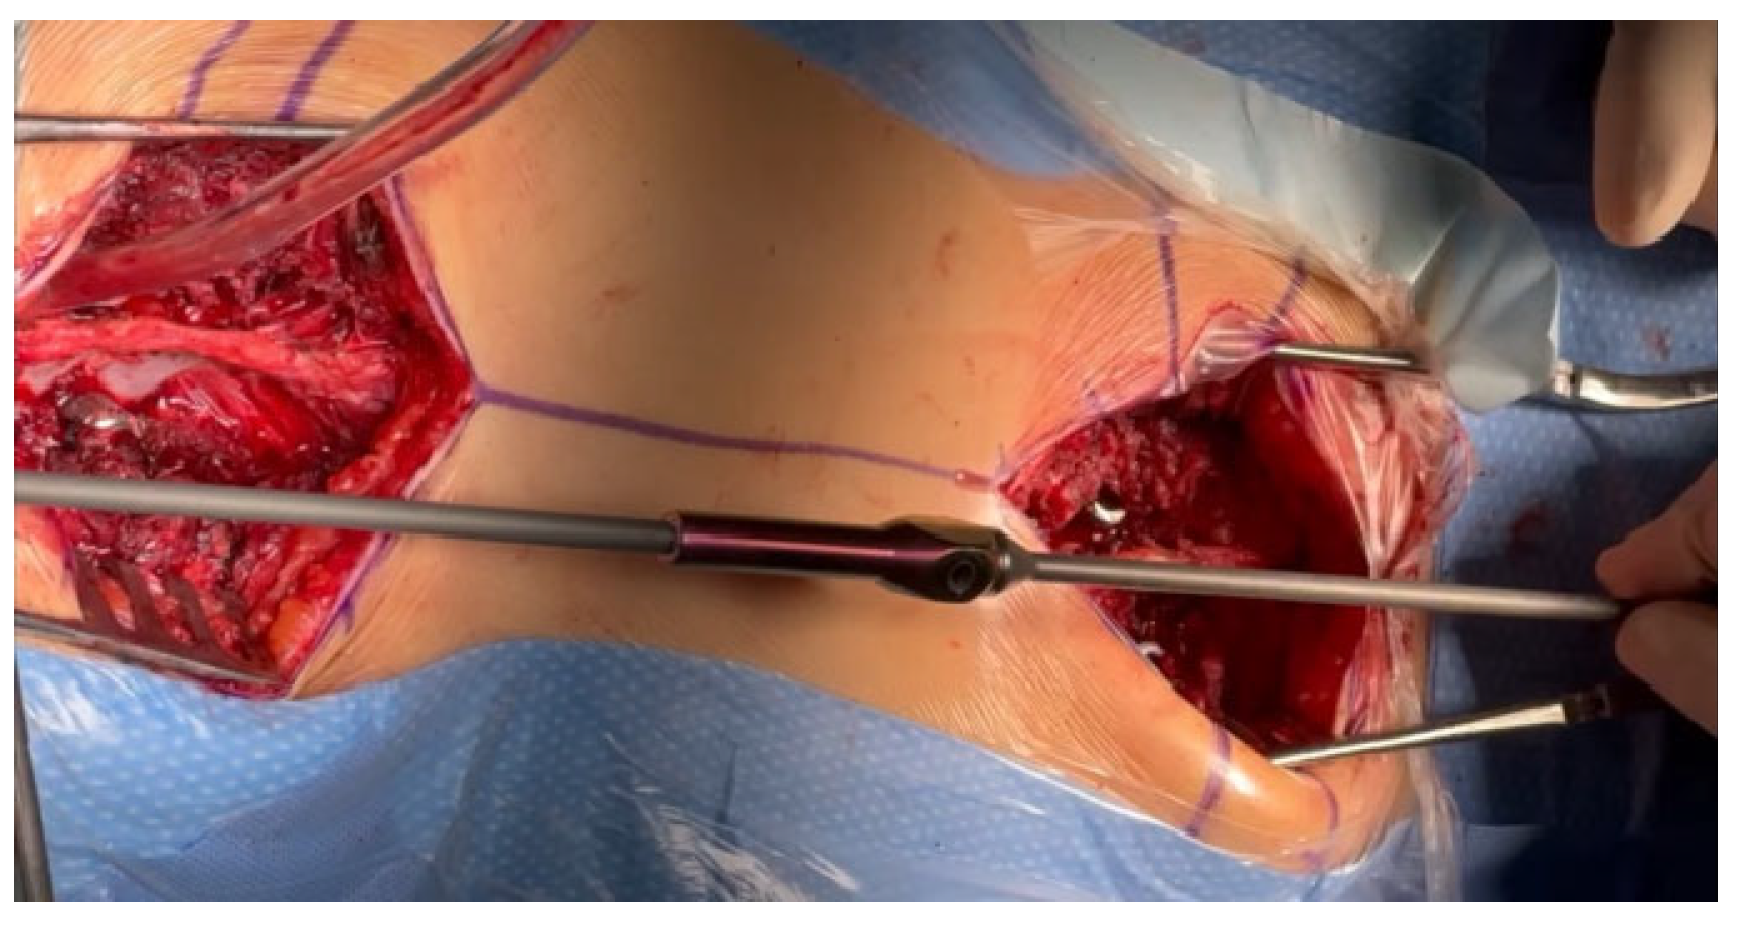

2.1. Surgical Technique